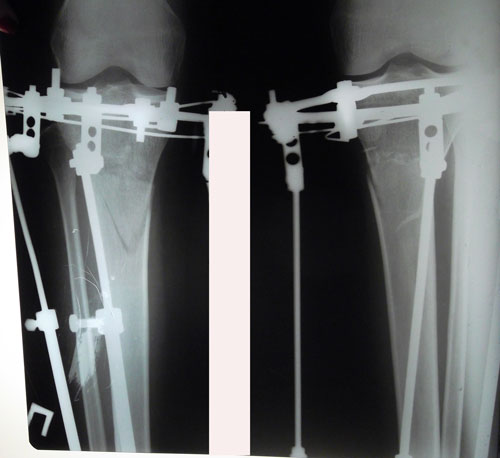

Исходник - 35 лет.

Укорочение правой ноги - 2 см.

Левая голень более деформирована.

Дата операции 22.03.2016г.

Дата снятия аппаратов 22.06.2016г.

Срок лечения 90 дней.

Диагноз: Укорочение правой ноги - 2 см.